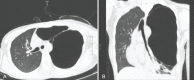

Vanishing lung syndrome

- Sharma N, Justaniah AM, Kanne JP, Gurney JW, Mohammed TL. Vanishing lung syndrome (giant bullous emphysema): CT findings in 7 patients and a literature review. J Thorac Imaging. 2009;24:227–30. - PubMed